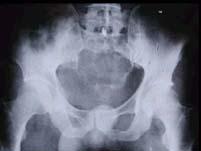

问题 有关脊索瘤好发部位和X线主要特点的描述中,你认为哪项不妥()

选项 A.肿瘤好发于脊椎两端,于中线部位 B.常为膨胀性溶骨性破坏,其中可残存碎骨片或小梁间隔 C.病变周围可出现软组织块影 D.50%患者可有钙化 E.绝大多数患者可有骨增生性反应

答案 E